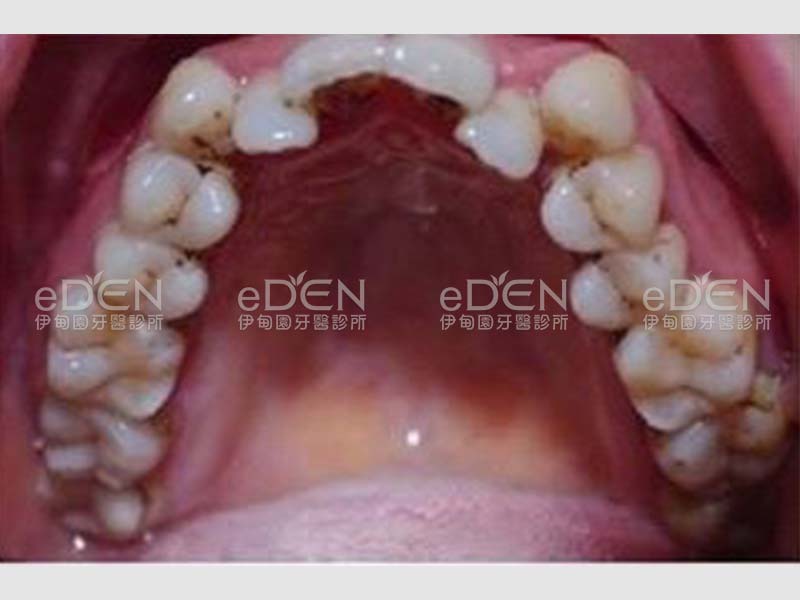

Invisalign Since 1997 長年追蹤35+年專業設計簡化時間 以人為本 選對醫師很重要,6-8歲骨性眠中矯正黃金期勿錯過 50-60歲牙周再生微矯正,專治困難厚道/暴牙/開咬(免開刀,免拔牙),解答您常年困擾問題。